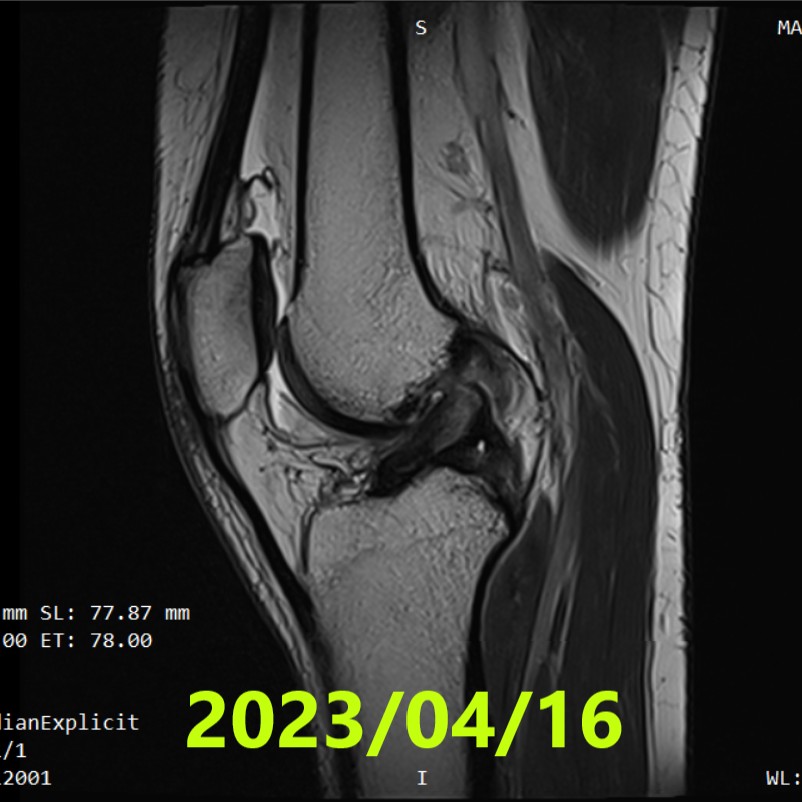

Evaluación inicial (RM #1)

- Fecha: 16 de abril de 2023

- Diagnóstico: rotura completa del LCA en la rodilla derecha + desgarro parcial del ligamento colateral medial

- Patrón de rotura: rotura proximal en la inserción femoral (tercio proximal)

- Clasificación de Ihara: II (Grado 2)

- Nota: no se realizó fisioterapia. La extensión completa de la rodilla se realizó solo durante el examen de RM

- RM #1 (2023/04/16): Ihara II (rotura proximal en la inserción femoral)